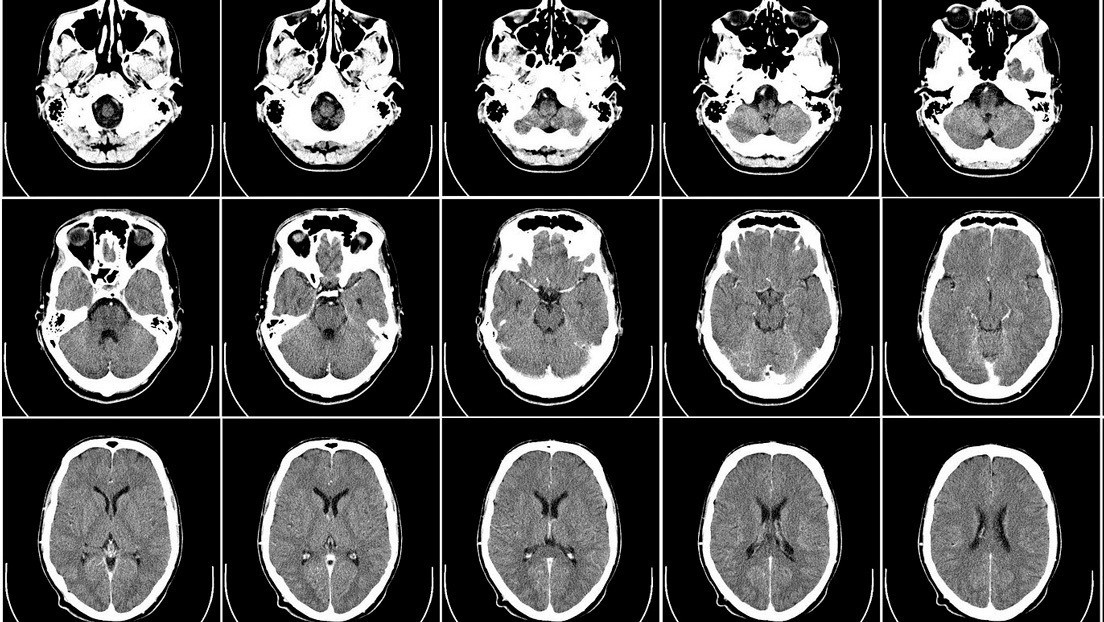

Un hombre que tenía como hobby la jardinería murió en Georgia (EE.UU.) tras contraer de una maceta una infección que acabó convirtiendo su cerebro en un líquido viscoso, según un estudio publicado la semana pasada en la revista New England Journal of Medicine.

La víctima, de 82 años, se expuso a tierra contaminada probablemente al llenar una maceta para sus plantas. A lo largo de las dos semanas siguientes, el hombre se fue debilitando y enfermando, hasta que tuvo que ser ingresado en un hospital.

El informe realizado por investigadores de la Universidad Emory en Atlanta señala que un día después de ser ingresado, el lado derecho de su cuerpo se debilitó completamente, además de desarrollar un "estado mental alterado" y diversos problemas cognitivos.